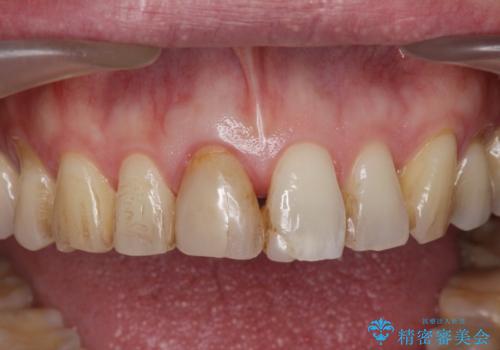

- 目立つ前歯の変色の改善を希望され来院されました。

根管治療を行いそのままにしていると歯は、徐々に変色を来します。